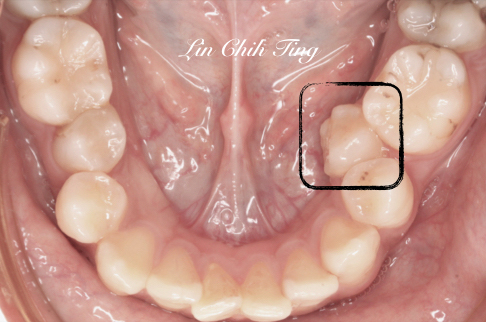

換牙時期若空間不足夠時,最慢萌發的牙常會被排擠。

此時千萬別放棄它,它是能被救回來的。

治療前